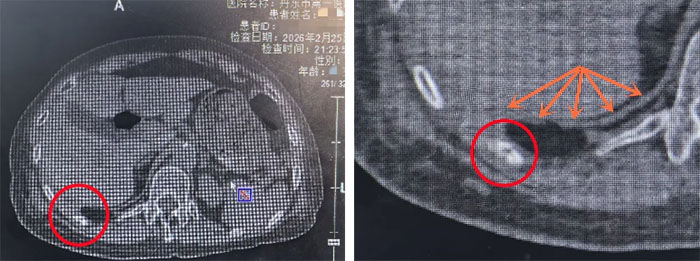

我院急诊科接诊医生看到刘阿姨的状态,立刻警觉起来。迅速为她完善胸部CT检查,结果显示:右侧肋骨骨折,右侧胸腔大量积液,高度怀疑是凶险的“血胸”。也就是说,她胸腔里可能正在持续出血。

(红色圆圈标注为骨折的肋骨“断茬”,黄色箭头为膈肌,两者间的距离很近)